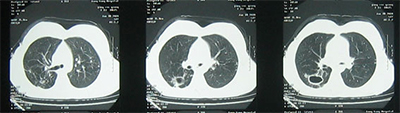

治療四個月后復(fù)查CT示:(2016年5月)

2016年5月初復(fù)查CT:與前片子相比病灶明顯吸收。根據(jù)藥敏結(jié)果進(jìn)一步調(diào)整了鞏固期的方案。5月10日患者出院,囑其規(guī)律用藥,定期復(fù)查,不適隨診。